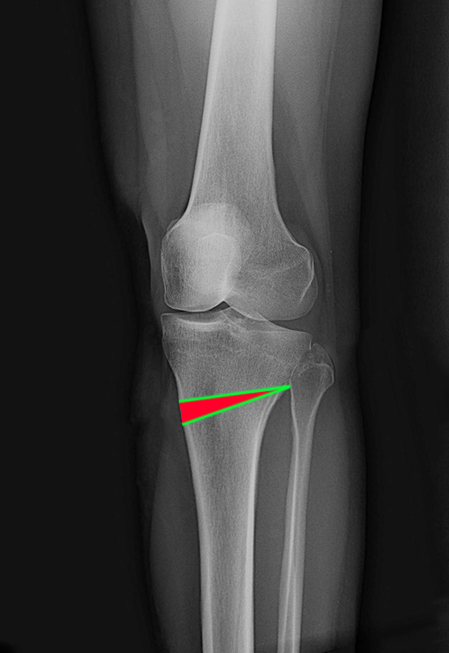

▲ 林女士左膝外側X光照

▲ 林女士左膝正面X光照,已接近膝蓋退化程度的第四期

最後別人介紹至□□醫院就醫,沒想到醫生看診不到1分鐘的時間就說要幫她安排最新的「高位脛骨截骨手術」,如此可使內側軟骨承重比例降低,能延後需要接受全人工關節置換手術的時間,以林女士的狀況來說,大概可以多撐個8年再來換人工關節。

▲ 在將近端小腿骨(脛骨)做出斜向的節骨切線

▲將截骨切口用自體骨、異體骨或是人工骨撐開至欲矯正的角度